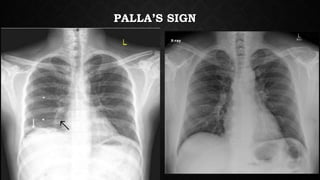

• Classically described signs such as the Hampton’s hump, Westermark

sign, Palla’s sign etc have a very poor sensitivity (<15%) and poor

positive predictive values.

PALLA’S SIGN